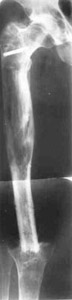

Tumour lower/third of right hip.

Removal of tumour with replacement of defect by means of Ilisarov's apparatus.

Closing of knee-joint.

Results of treatment.